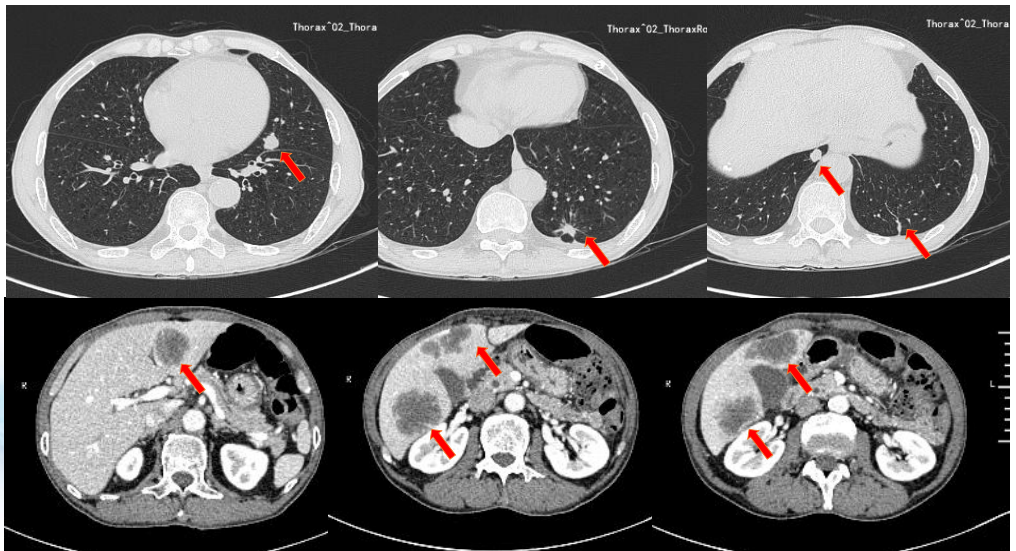

胸腹CT提示肝脏多发转移、双肺结节转移,腹腔淋巴结肿大(图2)。

图2. 胸腹部CT检查

初步诊断:直肠腺癌 cT3N2M1,多发肝、肺、骨、腹腔淋巴结转移。

影像学评估(截至2024年10月24日):肝、肺转移灶呈“缩小的SD”状态。

影像学评估(截至2025年2月27日):肝、肺转移瘤维持“缩小的SD”,骨转移瘤范围略增大。